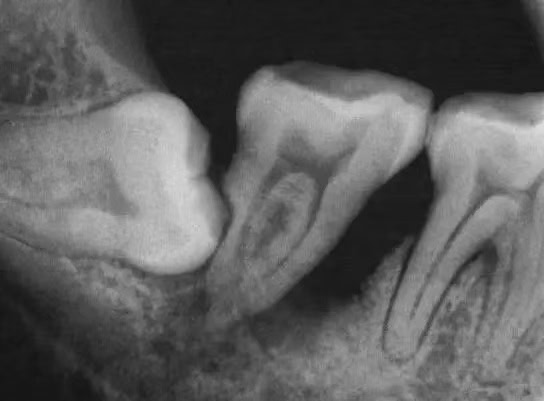

- X光片是評估智齒狀態的重要工具。通過X光片,牙醫師可以了解智齒的實際位置、方向、鄰近牙齒與顎骨的關係,以及是否存在潛在的問題如牙根吸收、囊腫或腫瘤等。

根據阻生智齒的位置和方向,拔除的難度和風險也會有所不同。垂直阻生相對較易處理,而近中阻生或遠中阻生可能需要更複雜的手術程序。阻生智齒的確切類型往往需要通過X光片或CBCT(錐形束計算機斷層攝影)等影像學檢查來確定,以便醫生能正確評估情況並規劃適當的治療方案。